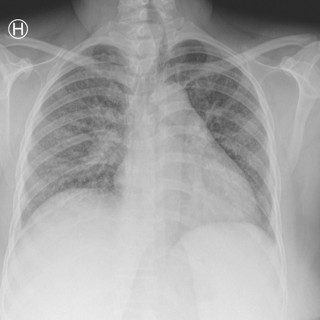

En yngre mann ble innlagt med venstresidige respirasjonsavhengige brystsmerter. Han hadde lett nedsatt allmenntilstand og feber. Det skulle bli et lengre sykehusopphold, der man diagnostiserte en uvanlig årsak til lungeaffeksjon. En tidligere frisk mann i slutten av tenårene ble via legevakt innlagt i sykehus etter ett døgn med venstresidige, respirasjonsavhengige smerter. Ved innkomst hadde han temperatur 37,6 °C, puls 117 slag/min, blodtrykk 104/57 mm Hg, respirasjonsfrekvens 24/min og perifer O2-metning på 94 % uten ekstra oksygentilførsel, og normale forhold ved klinisk undersøkelse...